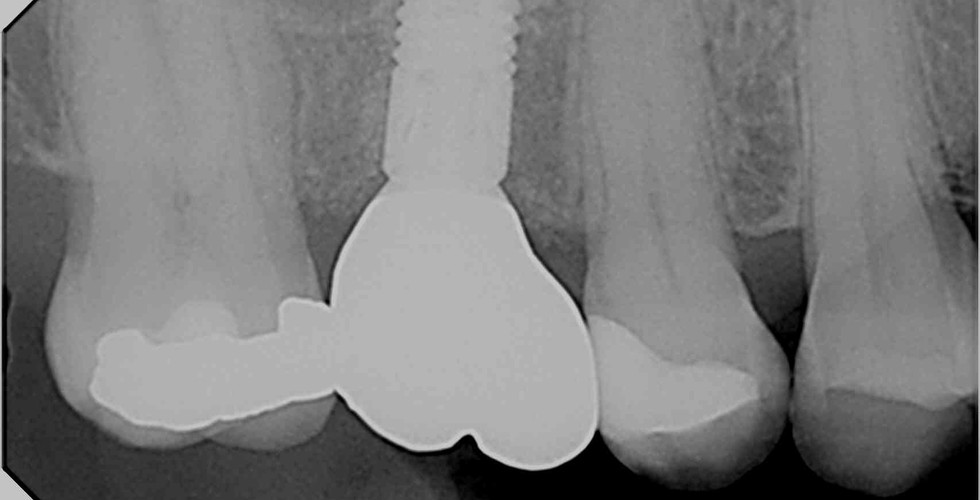

Another technique we regularly use is Guided bone regeneration (GBR). This is a surgical procedure used to encourage the growth of new bone in areas where it has been lost or is insufficient. It's often employed to augment the bone structure and provide a stable foundation for an implant. GBR utilises bone grafts and barrier membranes to create a protected space for bone regeneration.